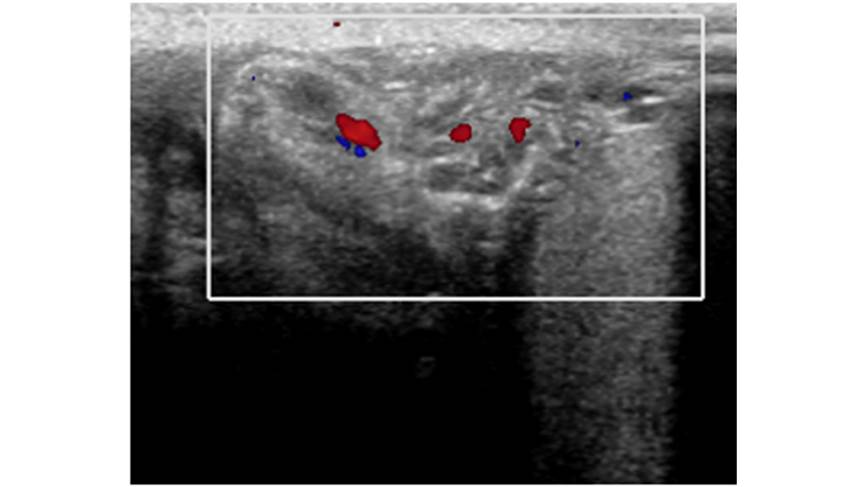

En el ultrasonido Doppler la vascularidad se observó incrementada proximalmente y una disminución del flujo sanguíneo distal, por lo que se hizo el diagnóstico de torsión testicular (Fig. 2). Sin embargo, con los cambios de temperatura con el uso del gel del transductor durante el estudio y la manipulación durante el estudio el dolor remitió, y al final del estudio se observa cómo se recupera el flujo sanguíneo y la posición normal testicular. Se establece el diagnóstico de torsión testicular izquierda intermitente.

Figura 2. Ultrasonido Doppler color con vascularidad incrementada proximal y disminución del flujo sanguíneo distal.

Figura 2 Ultrasonido Doppler